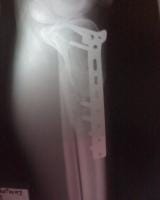

Doctor mi nombre es soy de la ciudad de Caracas Venezuela tengo 19 años de edad queria hacerle unas cuantas preguntas con respecto a mi fractura como lo indica el titulo una fractura metafisiaria de tibia izquierda el dia 01/01/09 ingrese al hospital y me indicaron que tenia que quedar internado hospitalizado durante 1 mes espere la operacion el dia 28/01/09 me operaron se me realizo una reduccion mas fijacion interna con placa lcp 4,5++ ingerto oseo en fisura de tibuia izquierda evolucione de forma satisfactoria y fui dado de alta el dia 30/01/09 acudi a control en el hospital pero devido a que me plantearon retiro de tornillo proximal, les plantie que necesitaba consultar con otros traumatologos y me indicaron que no era necesario devido a eso me retire del hospital y acudi a otro centro cree usted que sea el tipo de placa indicado el que me colocaron?.

Durante este tiempo los demas traumatologos me decian que no era necesario ya que la palca no presentaba rechazo, pero con respecto a eso doctor queria hacerle una pregunta tengo mi pierna hinchada en la parte inferior de la placa es visible la placa se puede palpar los tornillos mucho mas que antes.. Hace aproximadamente empeze a afincar sin amuletas y camino bien pero al caminar mucho se me hincha la pierna y me duele mucho espero que me ayude tengo algunas fotos que se las dejare a continuacion para que usted opine al respecto tengo tiempo que no me tomo algunas placas pero recientemente me hare una.. La cicatriz presenta una protuberancia al afincar solo se ve la protuberancia pero al dejar de afincar desaparece como una pelota que piensa usted al respecto? ¿Esto me ha sido un problema devido a que no he trabajado devido a que se me complica usted cree que pueda estar presentando un rechazo de la placa? ¿Termine mis terapias efectivamente y se me plantea reanudarlas usted cree que sea indicado? O ir al gimnacio a ejercitar la pierna los musculos.. Espero su pronta respuesta muchas gracias dr..